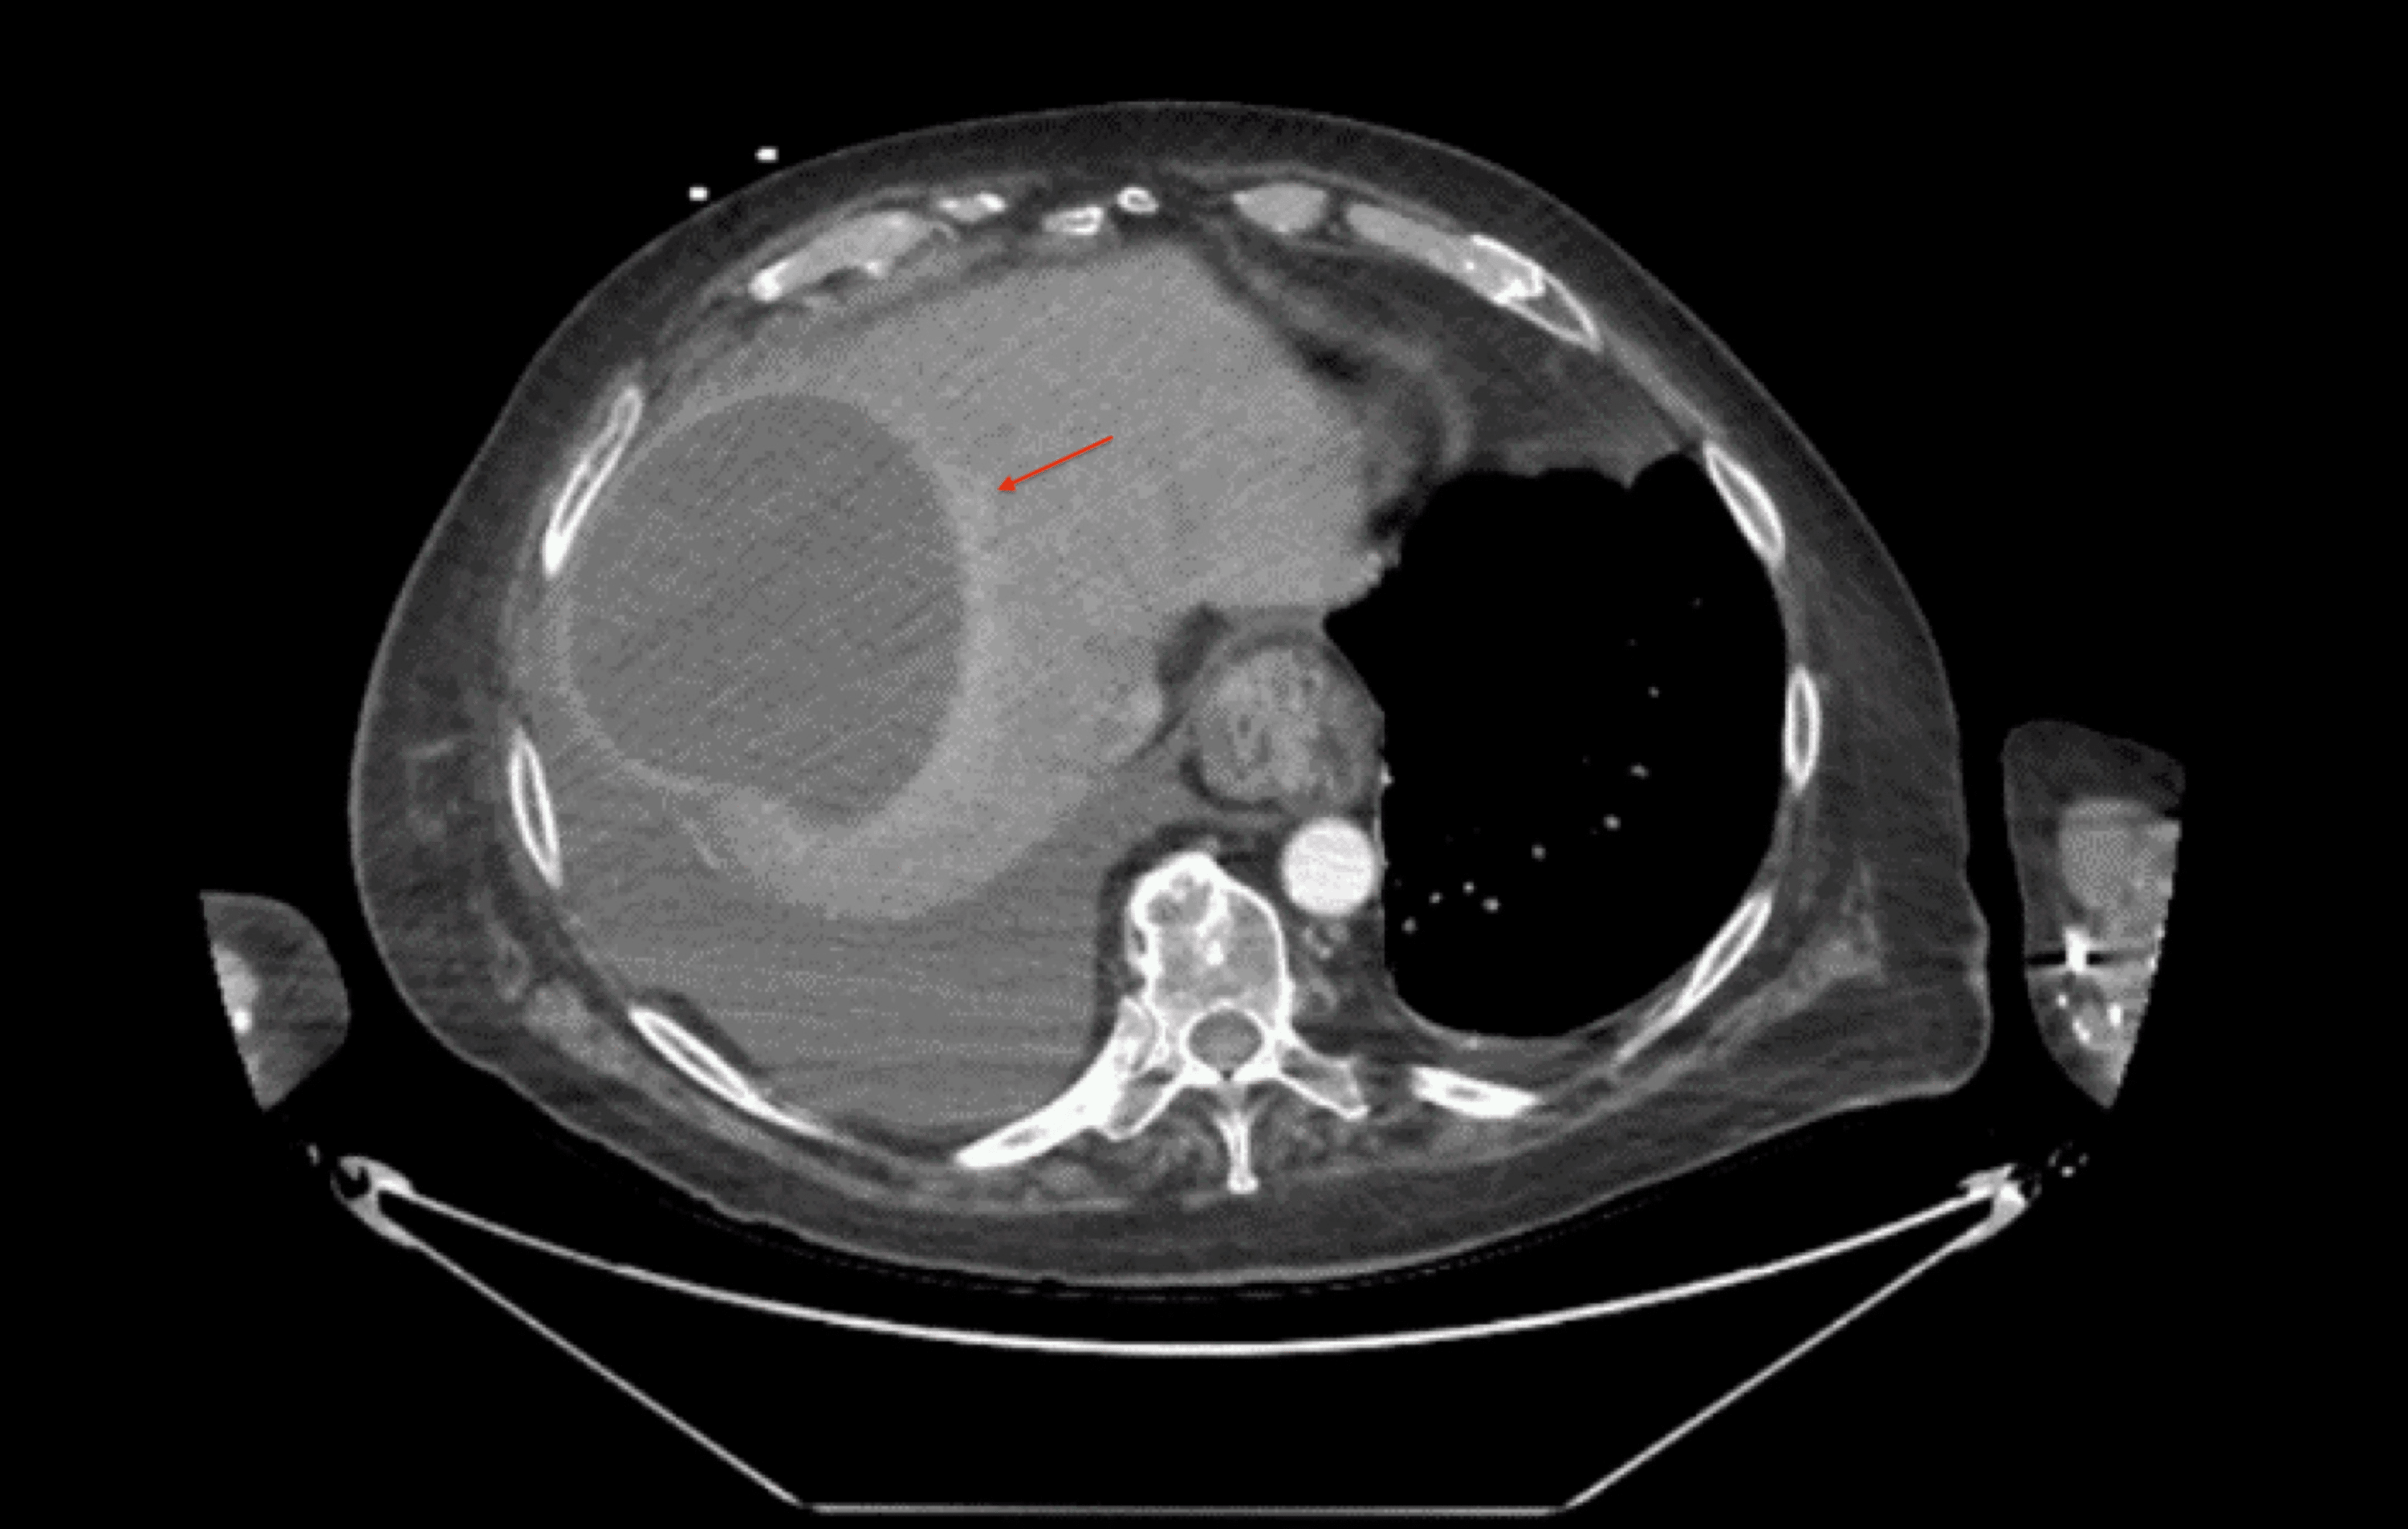

Pyogenic liver abscess CT wikidoc

From www.wikidoc.org

Pyogenic liver abscess CT wikidoc Ring Enhancement Liver Although the majority of liver metastases are hypodense and enhance less than the surrounding liver, metastases from certain. Peripheral arterial enhancement of focal liver lesions is an imaging feature that encompasses different patterns occurring in. Ring enhancement in ultrasmall superparamagnetic iron oxide mr imaging: Based on the enhancement pattern, we divide masses into hypervascular and hypovascular lesions. A potential new. Ring Enhancement Liver.